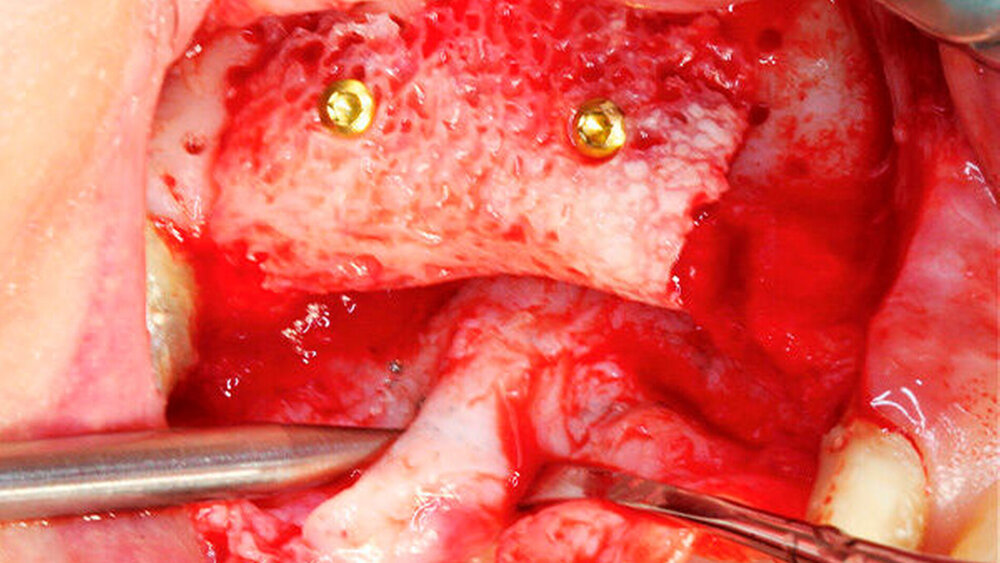

Die Schnittführung wurde nach dem Pillar-Sockel-Design (Blume) vorgenommen. Dabei liegt die Inzision weit im Vestibulum und verbindet zwei vertikale Entlastungsschnitte. Im Gegensatz zu der herkömmlichen krestalen Schnittführung bleibt das Periost über dem augmentierten Bereich damit völlig intakt. Nach der streng subperiostalen Präparation erfolgte die Kontrolle der Passung des CAD/CAM-Blocks. Ein ganz entscheidender Punkt ist, vor jeglichem Kontakt des Blockes mit Blut diesen in steriler Kochsalzlösung und am besten in der PRF-Flüssigkeit zu wässern, sodass sich keine Poren des Blocks mit Blutkoageln verschließen und innerhalb des Blocks ein nicht mit Blut gefüllter Hohlraum bildet. Vor der Befestigung des Blocks wurde die Kompakta des Empfängerbetts mit einer kleinen Kugelfräse mehrfach perforiert um sogenannte Bleeding Points zu setzen, die die Durchblutung des Knochenblocks gewährleisten. Mit zwei Osteosyntheseschrauben mit dem Durchmesser 1,5 mm und der Länge 9 mm wurde der allogene Knochenblock rotationssicher fixiert. Das Augmentat wurde mit einer dünnen Schweinepericard-Membran (Jason membrane, botiss biomaterials GmbH, Vertrieb Straumann) und der PRF-Membran abgedeckt. Der spannungsfreie Wundverschluss erfolgte mit der modifizierten vertikalen Matratzennaht nach Laurrell mit resorbierbarem Nahtmaterial (Vicryl 4.0). Postoperativ wurde ein Oberkiefer-DVT angefertigt. Die Nahtentfernung wurde im Rahmen der Nachsorgeuntersuchung sieben und 14 Tage postoperativ vorgenommen. Nach einer Heilzeit von sechs Monaten erfolgte die Implantation in Lokalanästhesie unter antibiotischer Abschirmung mit 2 g Amoxicillin oral eine Stunde präoperativ. Die Schnittführung erfolgte krestal, und nach subperiostaler Präparation wurde der Knochenblock dargestellt und die Osteosyntheseschrauben wurden entfernt. Danach wurden drei Implantate (Straumann) in den Knochenblock gesetzt und mit 0er-Verschlussschrauben abgedeckt. Die Wundrandadaptation erfolgte mit resorbierbarem Nahtmaterial, das bei der Verlaufskontrolle sieben Tage postoperativ vollständig entfernt wurde. Nach dreimonatiger gedeckter Einheilung wurden die Implantate im Rahmen einer Vestibulumplastik freigelegt. Dafür wurde eine erneute krestale Schnittführung regio 14 bis 17 vorgenommen und ein Splitflap präpariert. Der vestibuläre Wundrand wurde mit Einzelknopfnähten im Vestibulum fixiert. Im Bereich der Implantate wurde der Splitflap perforiert, um die Abdeckschrauben gegen Gingivaformer auszutauschen, und der Bereich des nun freiliegenden Bindegewebes wurde mit einer 3D-vernetzten Kollagenmatrix (mucoderm, botiss biomaterials GmbH, Vertrieb Straumann) abgedeckt. Diese wurde zunächst gewässert, um die Verarbeitung zu erleichtern, und an den Stellen der Gingivaformer gestanzt. Die Nahtentfernung erfolgte neun Tage postoperativ. (Abb. 1a bis 1f).